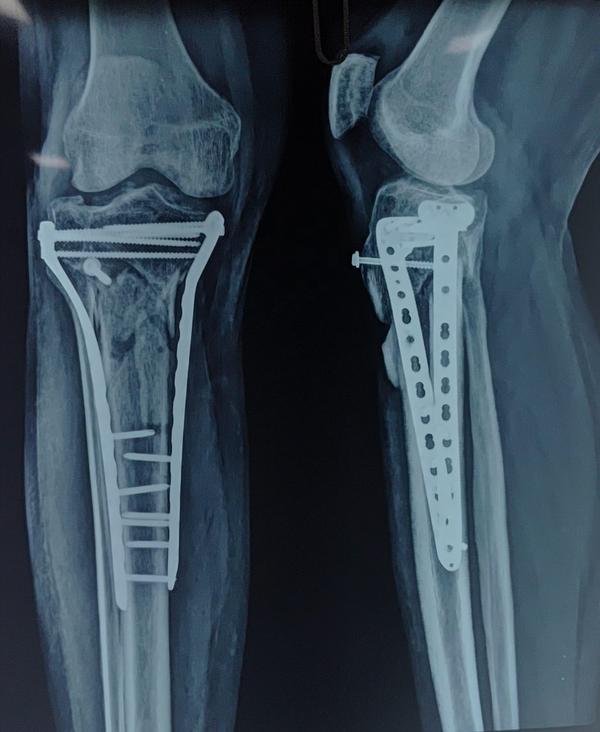

Fracture of Distal end Tibia and Fibula Fixation

Fracture of Distal end Tibia and Fibula Fixation.